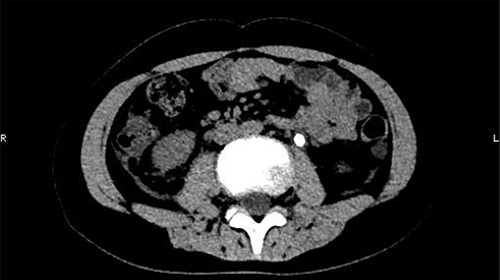

On 25 February, the patient complained of left back pain, nausea and vomiting. A further CT scan showed some irregular high-density shadows persisted in the left renal pelvis (Fig. 3) and an irregular high-density shadow was present in the left upper ureter (Fig. 4); furthermore, hydronephrosis was apparent in the left renal pelvis. There were no abnormalities in the bladder.

Some irregular high-density shadows persisted in the left renal pelvis, hydronephrosis was apparent in the left renal pelvis.